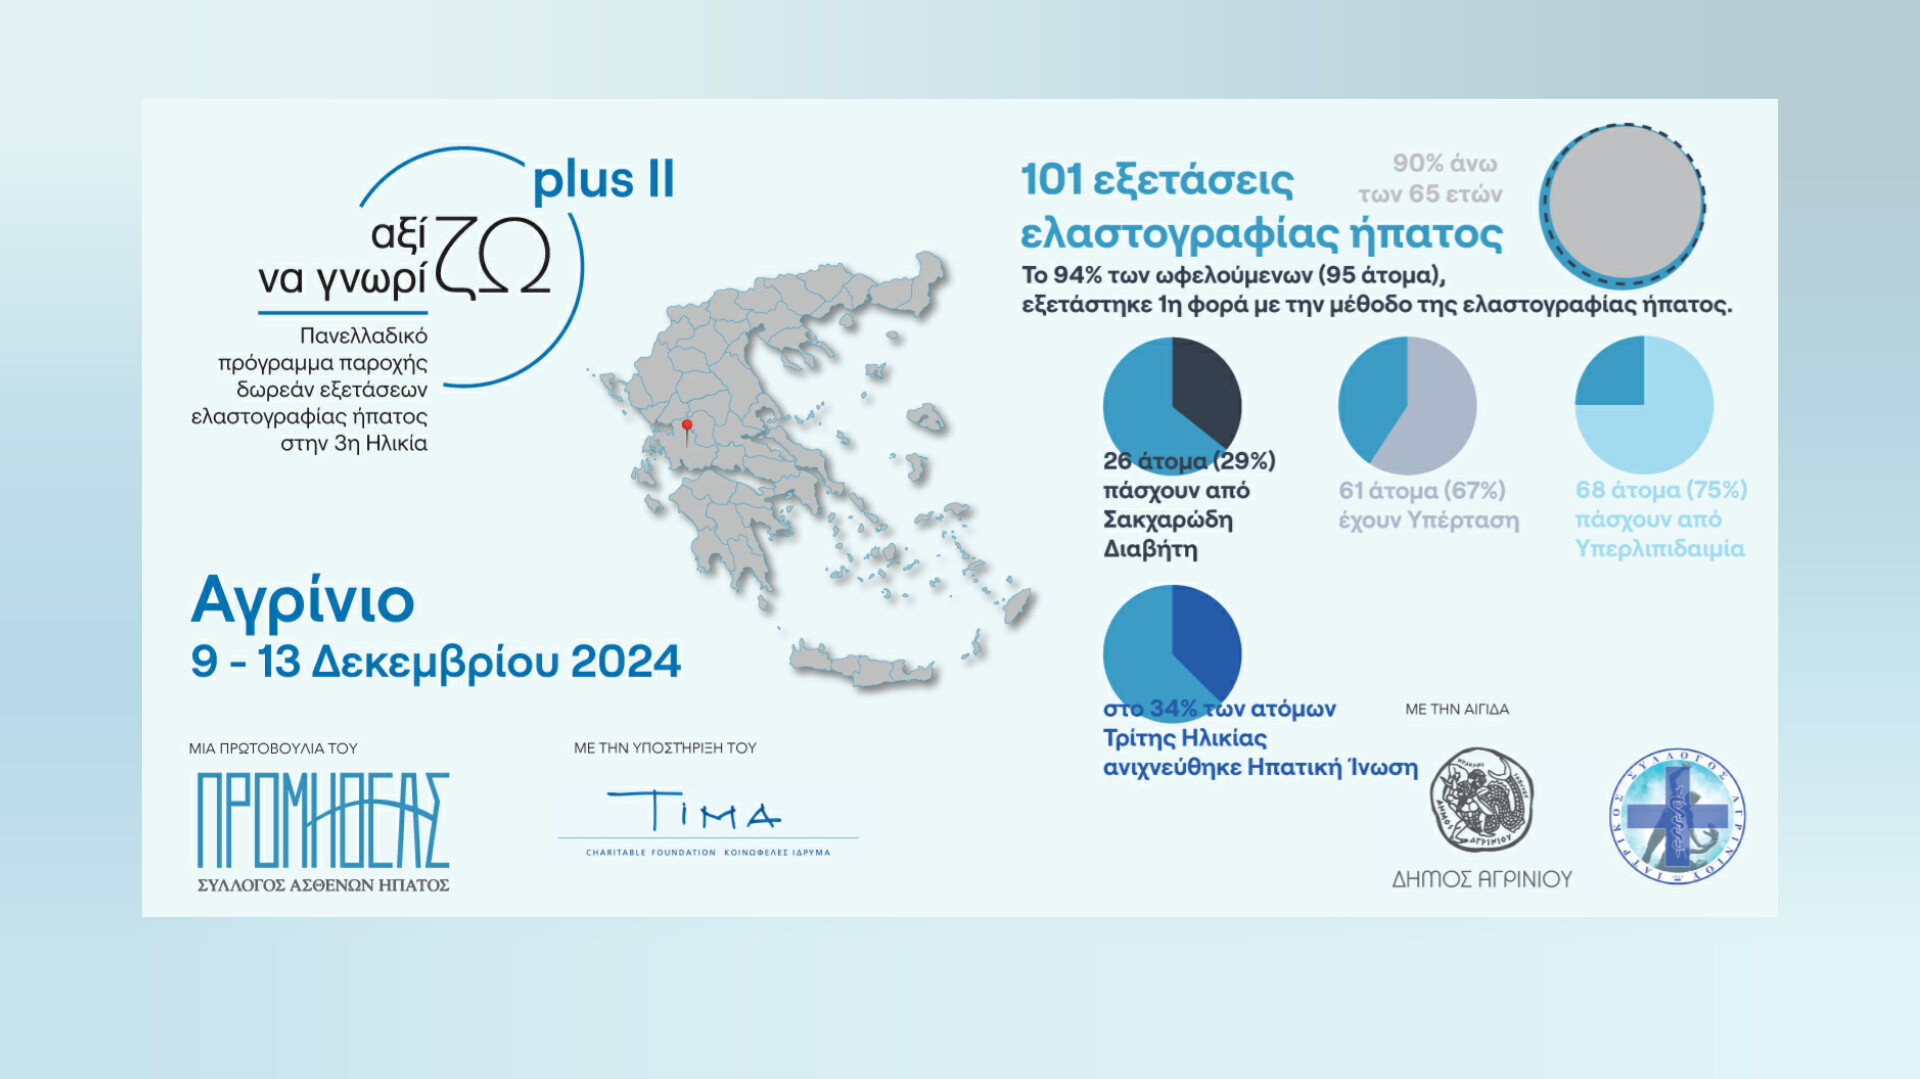

Το Αγρίνιο στο Πλευρό της Τρίτης Ηλικίας

Με επιτυχία και μεγάλη ανταπόκριση δημοτών ολοκληρώθηκε από τον Προμηθέα, η δεύτερη δράση του προγράμματος «Αξίζω να Γνωρίζω Plus ΙΙ» για την Τρίτη Ηλικία στο

Με επιτυχία και μεγάλη ανταπόκριση δημοτών ολοκληρώθηκε από τον Προμηθέα, η δεύτερη δράση του προγράμματος «Αξίζω να Γνωρίζω Plus ΙΙ» για την Τρίτη Ηλικία στο